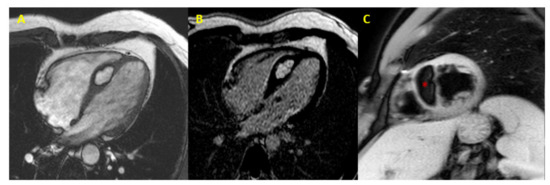

| Lymphoma | Right atrium | Malignant lymphocytes | T1 and T2 isointense, heterogeneous enhancement | Highly abnormal T2 relaxation times (up to 140 ms) with T2 -mapping | [29,30,31,32,33,34,35] |

| Metastases | Variable | Infiltrating malignant cells | Heterogeneous enhancement | [36,37,38,39] | |

| Metastases of melanoma | Variable | Infiltrating malignant cells | T1 hyperintense, T2 hypointense | Due to the T1 relaxation time-shortening properties of melanin | [40,41] |